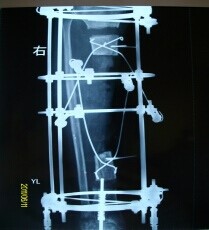

病例一:患者鹿XX,男,25岁,2011年1月3日发生车祸双下肢碾压伤,左下肢毁损,右胫骨开放性粉碎性骨折。外院急诊手术行左大腿截肢术,右小腿清创胫骨外固定支架固定术,术后右小腿感染,皮肤软组织坏死,长段胫骨外露,于2011年01月28日转来我院后行清创植皮修复等治疗。 于2011年05月07日行“右胫骨病灶清除+环形外固定支架固定+胫骨双段截骨滑移术”,术后开始行双段骨端滑移治疗(图一),根据X线片表现调整骨段滑移速度。2011年11月06日滑移骨段会师临床愈合。拆除外固定后2012年6月复查情况(图二)

图一 图二